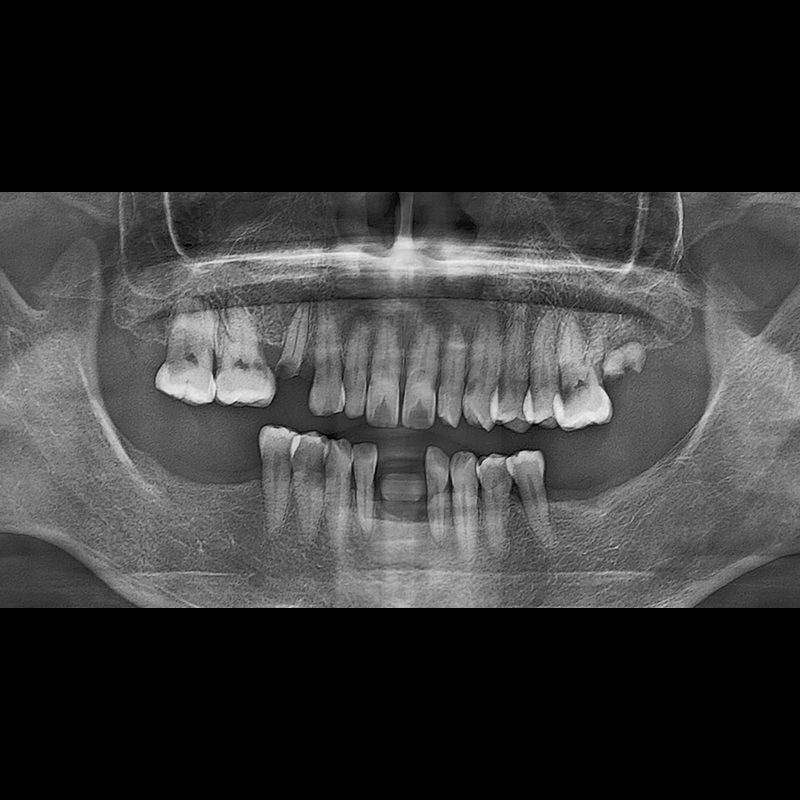

BEFORE AFTER

Implant before and after 2025.05.30

Implants were placed in the missing tooth and in the tooth position where it was difficult to save.